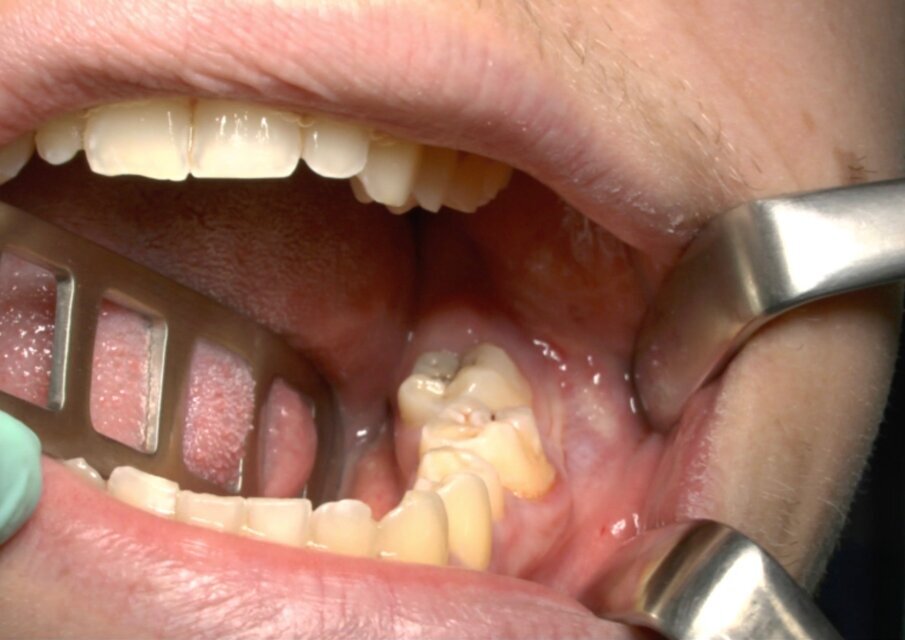

Protocollo standard

Ai pazienti viene prescritta una profilassi antibiotca con 2 gr di amoxicillina 1 h prima dell’intervento, si esegue quindi un anestesia di tipo tronculare con lidocaina senza vasocostrittore, poi infiltrazione di tipo plessica con adrenalina in corrispondenza del nervo buccinatore. Si scolpisce quindi un lembo a tutto spessore di tipo triangolare con incisione orizzontale alla base delle papille tra sesto e settimo ed incisione di scarico distale con andamento vestibolare (Figg. 1-4). Si procede con l’osteotomia che può essere eseguita con strumenti rotanti montati su manipolo retto oppure con terminale piezoelettrico con gli inserti dedicati. Qualora sia necessario si effettua l’odontotomia e la separazione radicolare con frese al carburo di tungsteno montate su turbina, quindi si esegue la lussazione e l’avulsione dell’elemento dentario. Si procede alla revisione della cavità alveolare con abbondante lavaggio con soluzione fisiologica, riempimento con collagene e sutura a punti staccati in seta 4/0. Il paziente viene dimesso con terapia analgesica ed antibiotica di supporto (Figg. 5-15).

Fig. 7_Ostectomia completata.

Fig. 8_Odontotomia. Il taglio si trova fra la zona di massima circonferenza e la giunzione smalto cemento.